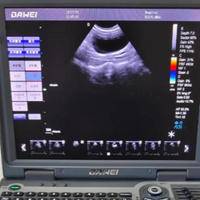

盆底肌检查和阴超哪个疼,一文了解真相减少焦虑

在妇科与产后康复相关的检查中,盆底肌功能评估与阴道超声(简称“阴超”)是两项常见且重要的检查项目。许多女性,尤其是产后或存在特定症状的患者,往往会对这两项检查的体验感到担忧和好奇,事实上,这两种检查在目的、操作方式和体感上存在显著差异,其带来的不适感也因人而异,并非简单的“疼痛”可以概括。本文将深入解析两者的具体过程与感受,帮助您在了解的基础上减轻不必要的紧张情绪。盆底肌检查和阴超疼痛解析阴超的体...

盆底肌检查和阴超哪个会更疼一些呢?

一般来说,阴超可能会比盆底肌检查稍微疼痛一些。阴超是通过将超声探头插入阴道进行检查,可能会引起一些不适或轻微的疼痛感,特别是对于那些对阴道接触比较敏感的人来说。通常情况下,医生会使用适当的润滑剂以减少不适感。盆底肌检查包括的内容比较广泛,可能包括检查盆底肌肉的紧张度、协调性以及对不同刺激的反应等。这种检查一般是通过在外阴和肛门周围放置电极来测量肌肉的电活动,不会直接涉及到阴道内部。